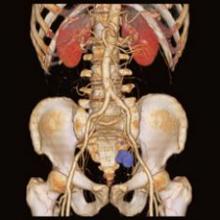

August 30, 2007 – Medrad has released the Pres Pressure-Rated Extension Set, the only extension set that is rated for computed tomography (CT) power injection and specifically approved for Medrad CT contrast injection systems.

An extension set, which is commonly used in conjunction with IV access, is a disposable tube set that attaches the patient catheter and the power injector tubing. The U.S. Food and Drug Administration recommends using only venous access devices that are compatible with the high pressures achieved when power injecting.

August 31, 2007 - Toshiba America Medical Systems Inc., a global provider of diagnostic medical imaging systems and comprehensive medical solutions, announced that East Tennessee Children’s Hospital has installed two Aquilion computed tomography (CT) systems, one 16-slice and one 64-slice, into its facility.